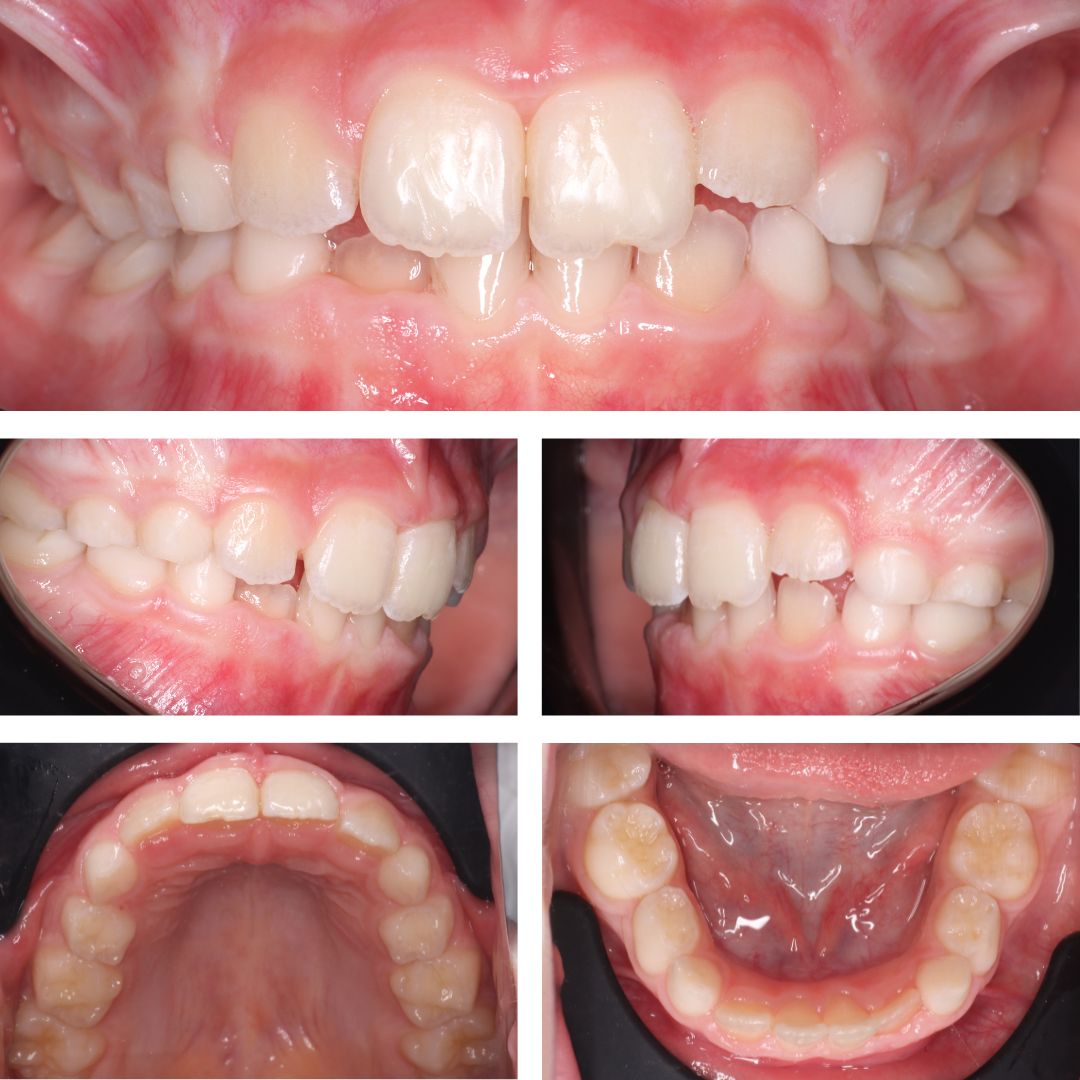

👉 Каппы Kinder Smile разработаны компанией STAR SMILE для ортодонтического лечения в период активной смены молочных зубов на постоянные. Каппы незаметны во рту, действуют мягко, не вызывая боли, не ограничивают образ жизни и диету, поэтому для ребенка процесс лечения проходит максимально легко, что и было подтверждено в ходе данного лечения, которое заняло 5 месяцев.

Посмотрите фото ДО и ПОСЛЕ. Как вам такое 🔥 преображение?

Мастер преображения 😁 улыбки врач-ортодонт Ирина Константиновна Шевченко.